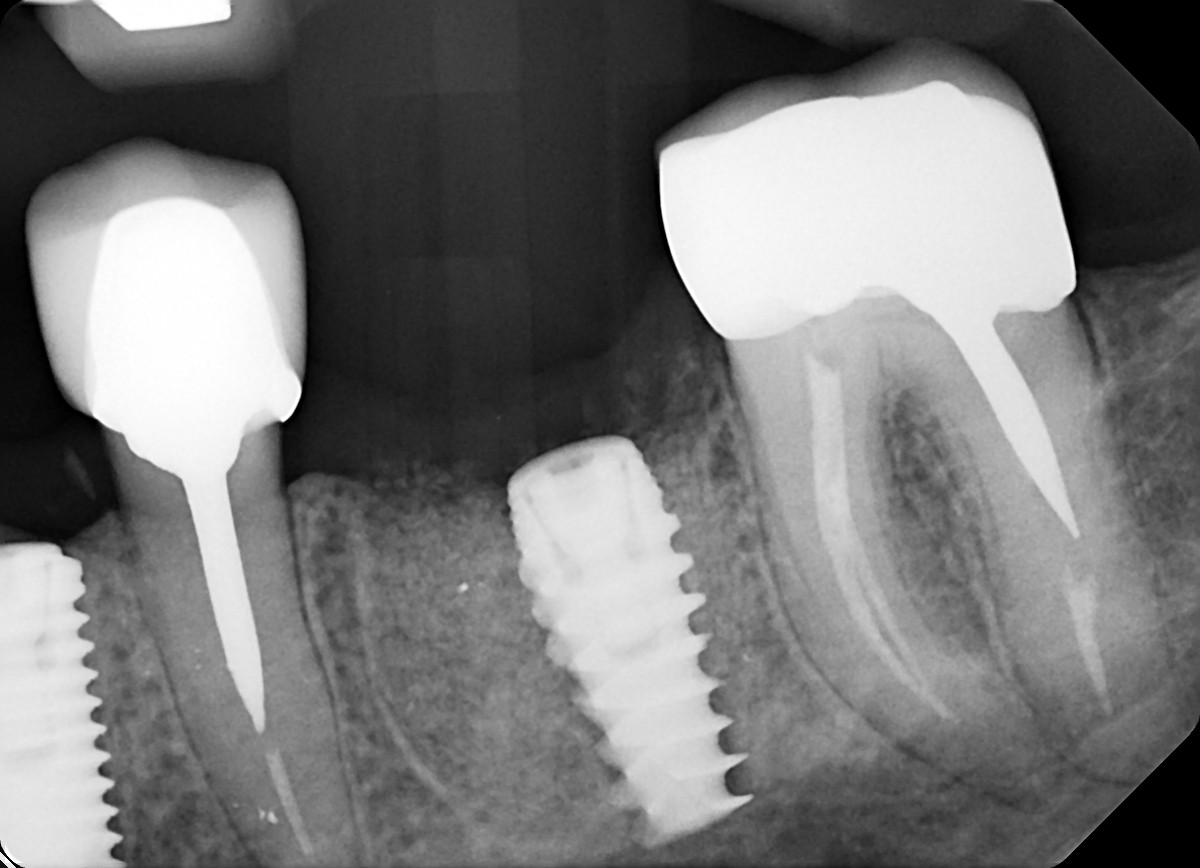

1. What option can explain the crown of the tooth # 1.4?

10. What option can explain the restoration on the implant?